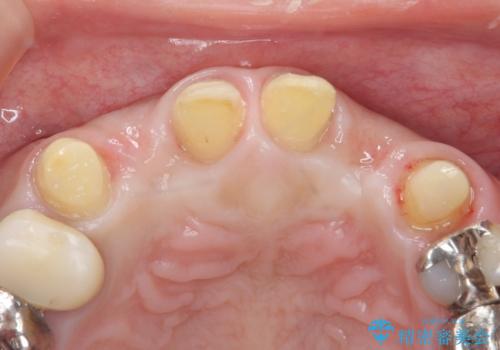

- 前歯のがたつきが気になるとの事で来院。

①矯正を行う(費用と時間がかかる)

②左右2番の歯を抜歯してブリッジの被せ物を入れる(矯正ほど費用、時間はかからない)

という計画を立てて患者様に選んでもらいました。

②の方を選択されましたので被せ物治療を行いました。

また、左上の犬歯の根の再治療も行いました。